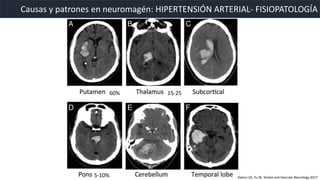

• Efecto sistémico de la presión en las arterias pequeñas penetrantes.

• Desarrollo de hiperplasia e hialinizacion de la intima y degeneración

de la media. Predispone a necrosis focal y ruptura.

• Desarrollo de micro aneursimas (Charcot Bouchard), que se rompen y

resultan en sangrado.

Causas y patrones en neuromagén: HIPERTENSIÓN ARTERIAL- FISIOPATOLOGÍA

Jeremy J. et al. Imaging of Intracranial Hemorrhage. Journal of Stroke 2017

60% 15-25

5-10% Dastur CK, Yu W. Stroke and Vascular Neurology 2017

• Los sangrados originados en los ganglios

basales y tronco cerebral tienen mayor

probabiliad de extensión al sistema

ventricular.

• Microsangrados en la distribución de los

vasos pequeños perforantes.

• Consecuencia de la arteriopatia

hipertensiva resultante en sangrado de

volumen pequeño que es generalmente

crónico y multifocal.

• MR: Microsangrado focal con perdida de

señal < 10mm

Causas y patrones en neuromagén: HIPERTENSIÓN ARTERIAL- LOCALIZACIÓN